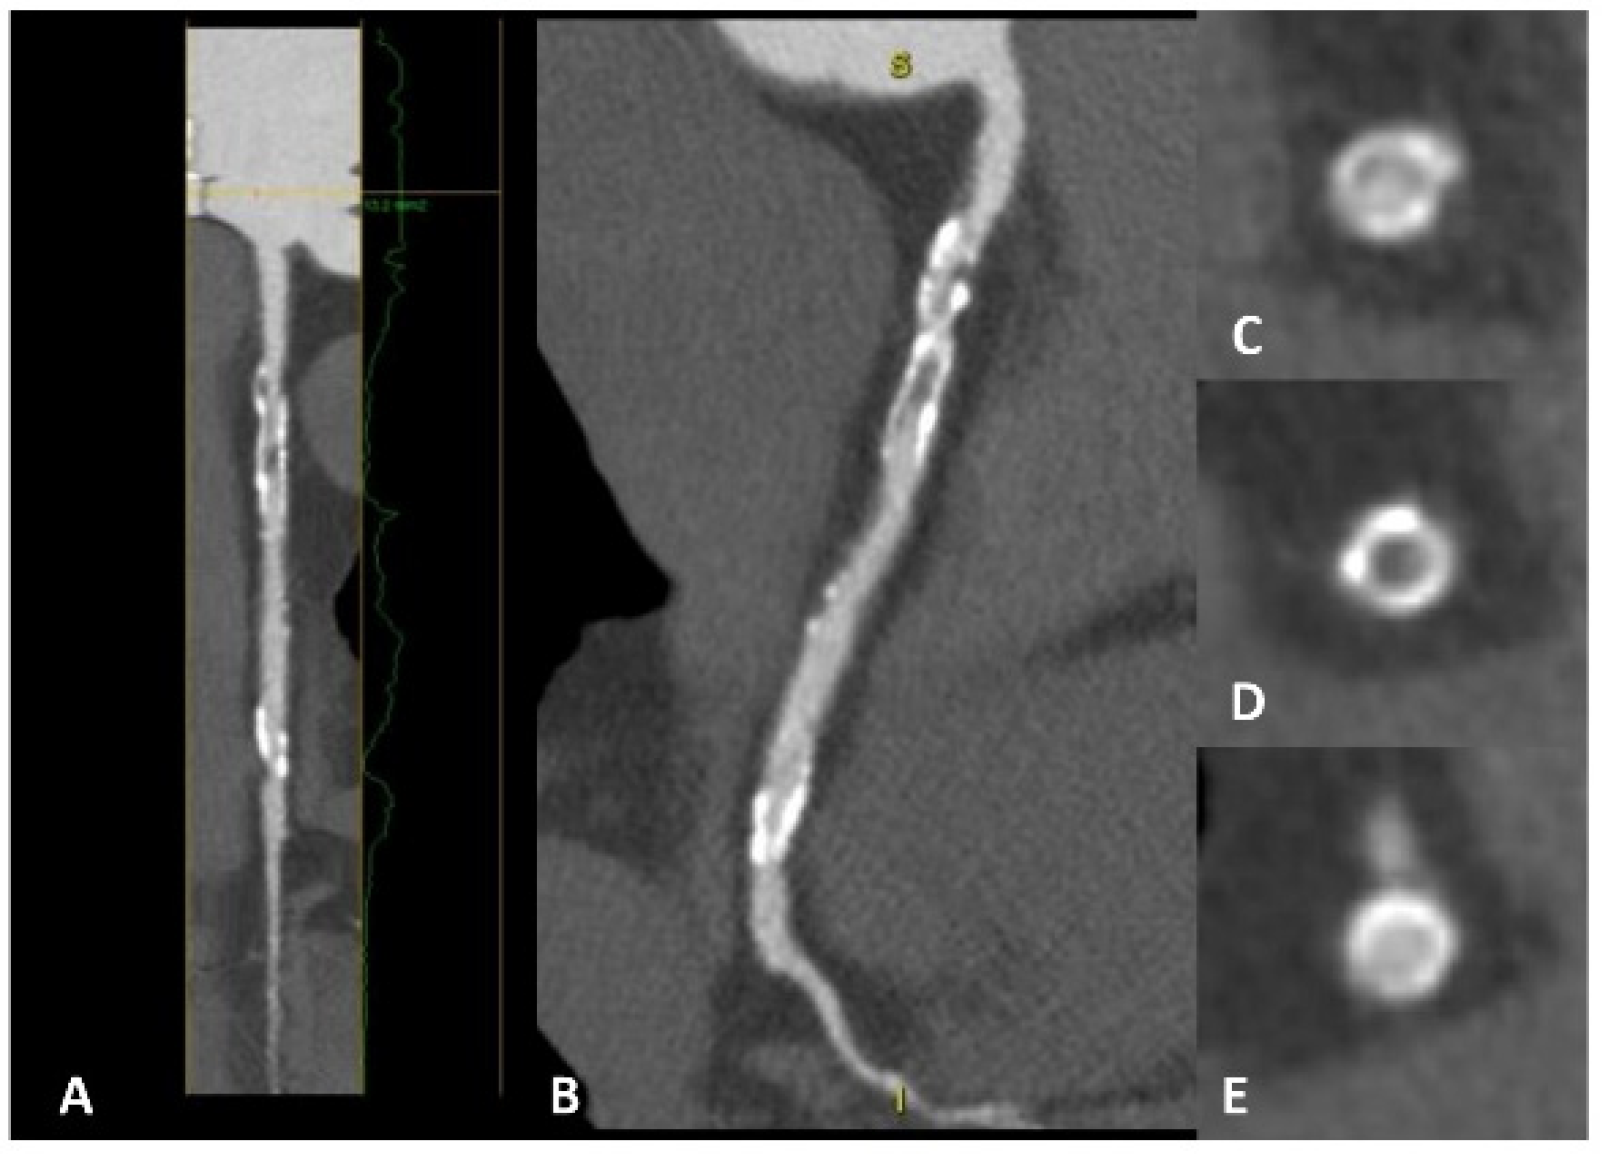

5.1. Calcium Scoring and Beyond for Primary Prevention